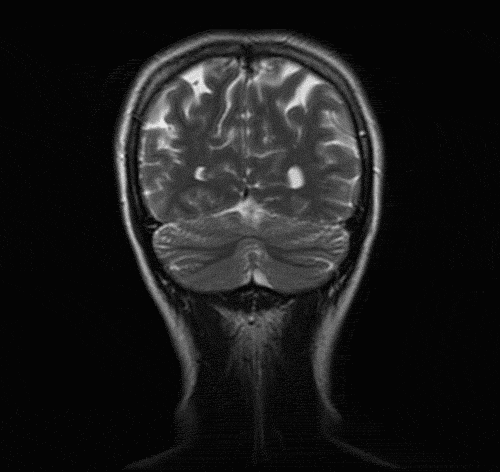

© Pinterest 音乐如何作用于大脑的情绪中枢? 在探究音乐与情绪的关系的科学研究中 , 最有趣的领域之一便是对大脑的研究 , 它提出的问题是:音乐是否触发了大脑情绪控制系统的特定区域?这个过程和音乐本身的情绪有关吗?答案似乎是肯定的 。 2014年发表于《自然》(Nature)杂志的一项突破性研究成果发现 , 音乐与大脑的多个区域有着确切的联系 , 其中许多都和情绪的触发过程紧密相关 。 有意思的是 , 紧张和期望的解释还真的占有一席之地 。 研究发现 , 创造愉悦情绪的音乐点亮了中脑边缘通路(又称奖赏途径 , 是脑中的多巴胺通路) , 而那恰好是给人带来愉悦奖赏的大脑机制所在区域 。 不仅如此 , 音乐还能触发杏仁核(搭建情绪网络)和海马体(调节依恋关系方面的情绪)的响应 。 可以肯定的是 , 愉悦感的确部分来自于紧张情绪的产生及释放 , 尽管并非全部如此 。